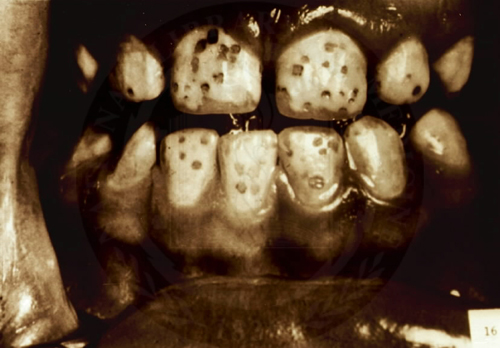

Aceleasi teorii aduc argumente in privinta pericolelor ingerarii de fluor, punand accentul pe toxicitatea sa si pe efectele nocive, pe termen lung, asupra sanatatii, efecte despre care publicul stie prea putin. Ei citeaza in primul rand un studiu foarte amplu, realizat la sfarsitul anilor ’80 pe 39.000 de copii americani, studiu care a aratat ca nu au aparut diferente semnificative in ceea ce priveste numarul de carii intre copiii care bausera si cei care nu bausera apa fluorizata. Deci, fluorul n-ar avea mult laudatul efect de a preveni aparitia cariilor. In schimb, specialistii afirma ca supradozarea fluorului, ca urmare a ingestiei de fluoruri continute in apa de baut, determina aparitia fluorozei dentare, o afectiune caracterizata prin fragilizarea dintilor si aparitia de pete pe suprafata lor. Riscul e si mai mare in conditiile in care consumului de apa fluorizata i se adauga alte surse de fluor: suplimente cu fluor (ce-i drept, prescrise adesea copiilor inca din pruncie) sau expunerea la poluarea produsa de carbunele cu continut mare de fluor.